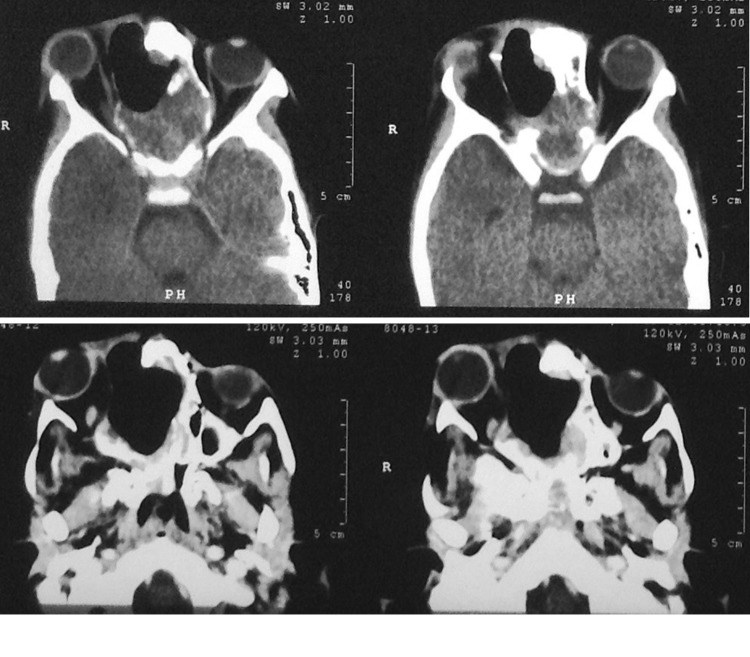

Fig. 2.

Case 2—post op CT after subtotal excision via lateral rhinotomy

Fig. 3.

Case 2—sagittal and Coronal CT scan 1 month post op showing regrowth of lesion